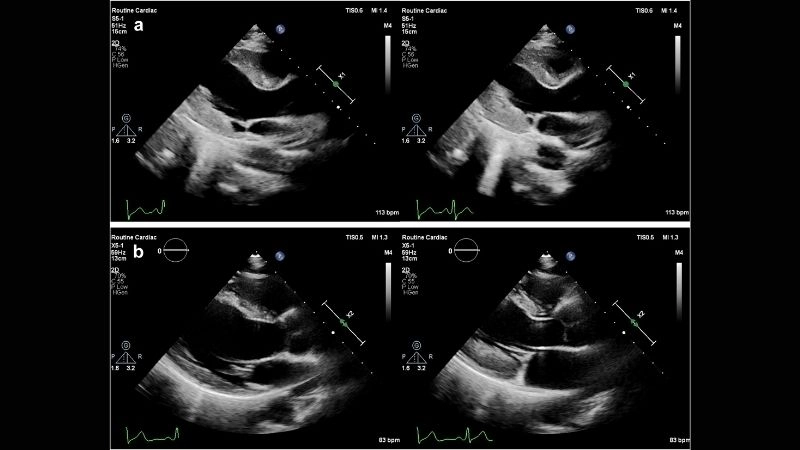

Images visual examples of eosinophilic myocarditis

Eosinophilic myocarditis is a rare inflammatory heart disease where eosinophils damage the cardiac muscle, causing weakness, chest pain, and sometimes severe complications like heart failure.